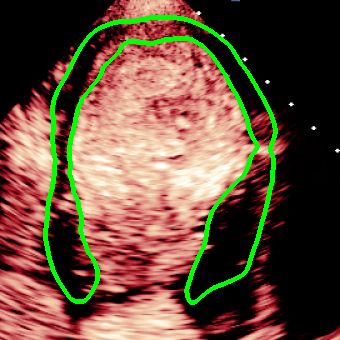

For variations caused by low quality images such as those of low resolution or significant artifacts, however, the unique ground truth may not be available. Take the myocardial segmentation task of Myocardial Contrast Echocardiography (MCE) as an example. An inter-observer experiment was conducted among five experienced cardiologists, and Fig. 1(a)(b) visualize the annotations of two images from three of these cardiologists. It can be seen that the labels by different cardiologists vary significantly, especially in locations where the intensity information of myocardium is very similar to the background. Table 1 shows the average Dice of the annotation of each cardiologist, using one of the others’ as the ground truth, over 180 images. We can observe that none of the Dice is above 0.9, some even under 0.8, confirming significant variations among the annotations. In this case, as the variations are caused by the image quality, even these cardiologists cannot tell which annotation is better than others, and a majority vote for ground truth would not make sense sometimes as can be seen in Fig. 1(c)(d). For this reason, we cannot obtain a unique ground truth in the evaluation process and the traditional metrics such as Dice and IoU cannot be used.